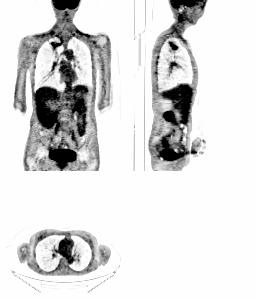

Illustration : à gauche un PET corps entier au FDG (résolution spatiale environ 6mm) et à droite un scanner X du même patient (résolution de l'ordre du mm).

L'analyse multirésolution des deux sets d'images puis leur combinaison permet d'aboutir à l'image suivante :

On dispose alors de l'information fonctionnelle du PET scan (avec entre autre une activité tumorale pulmonaire significative) avec la résolution spatiale du scanner X. En particulier les poumons sont mieux délimités.